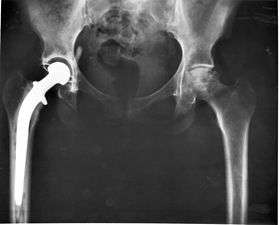

Some examples include pacemakers, infusion pumps, the heart-lung machine, dialysis machines, artificial organs, implants, artificial limbs, corrective lenses, cochlear implants, ocular prosthetics, facial prosthetics, somato prosthetics, and dental implants.

- Class III devices generally require premarket approval (PMA) or premarket notification (510k), a scientific review to ensure the device's safety and effectiveness, in addition to the general controls of Class I. Examples include replacement heart valves, hip and knee joint implants, silicone gel-filled breast implants, implanted cerebellar stimulators, implantable pacemaker pulse generators and endosseous (intra-bone) implants.

Implants

An implant is a kind of medical device made to replace and act as a missing biological structure (as compared with a transplant, which indicates transplanted biomedical tissue). The surface of implants that contact the body might be made of a biomedical material such as titanium, silicone or apatite depending on what is the most functional. In some cases, implants contain electronics, e.g. artificial pacemakers and cochlear implants. Some implants are bioactive, such as subcutaneous drug delivery devices in the form of implantable pills or drug-eluting stents.

Artificial body part replacements are one of the many applications of bionics. Concerned with the intricate and thorough study of the properties and function of human body systems, bionics may be applied to solve some engineering problems. Careful study of the different functions and processes of the eyes, ears, and other organs paved the way for improved cameras, television, radio transmitters and receivers, and many other useful tools. These developments have indeed made our lives better, but the best contribution that bionics has made is in the field of biomedical engineering (the building of useful replacements for various parts of the human body). Modern hospitals now have available spare parts to replace body parts badly damaged by injury or disease [Citation Needed]. Biomedical engineers work hand in hand with doctors to build these artificial body parts.